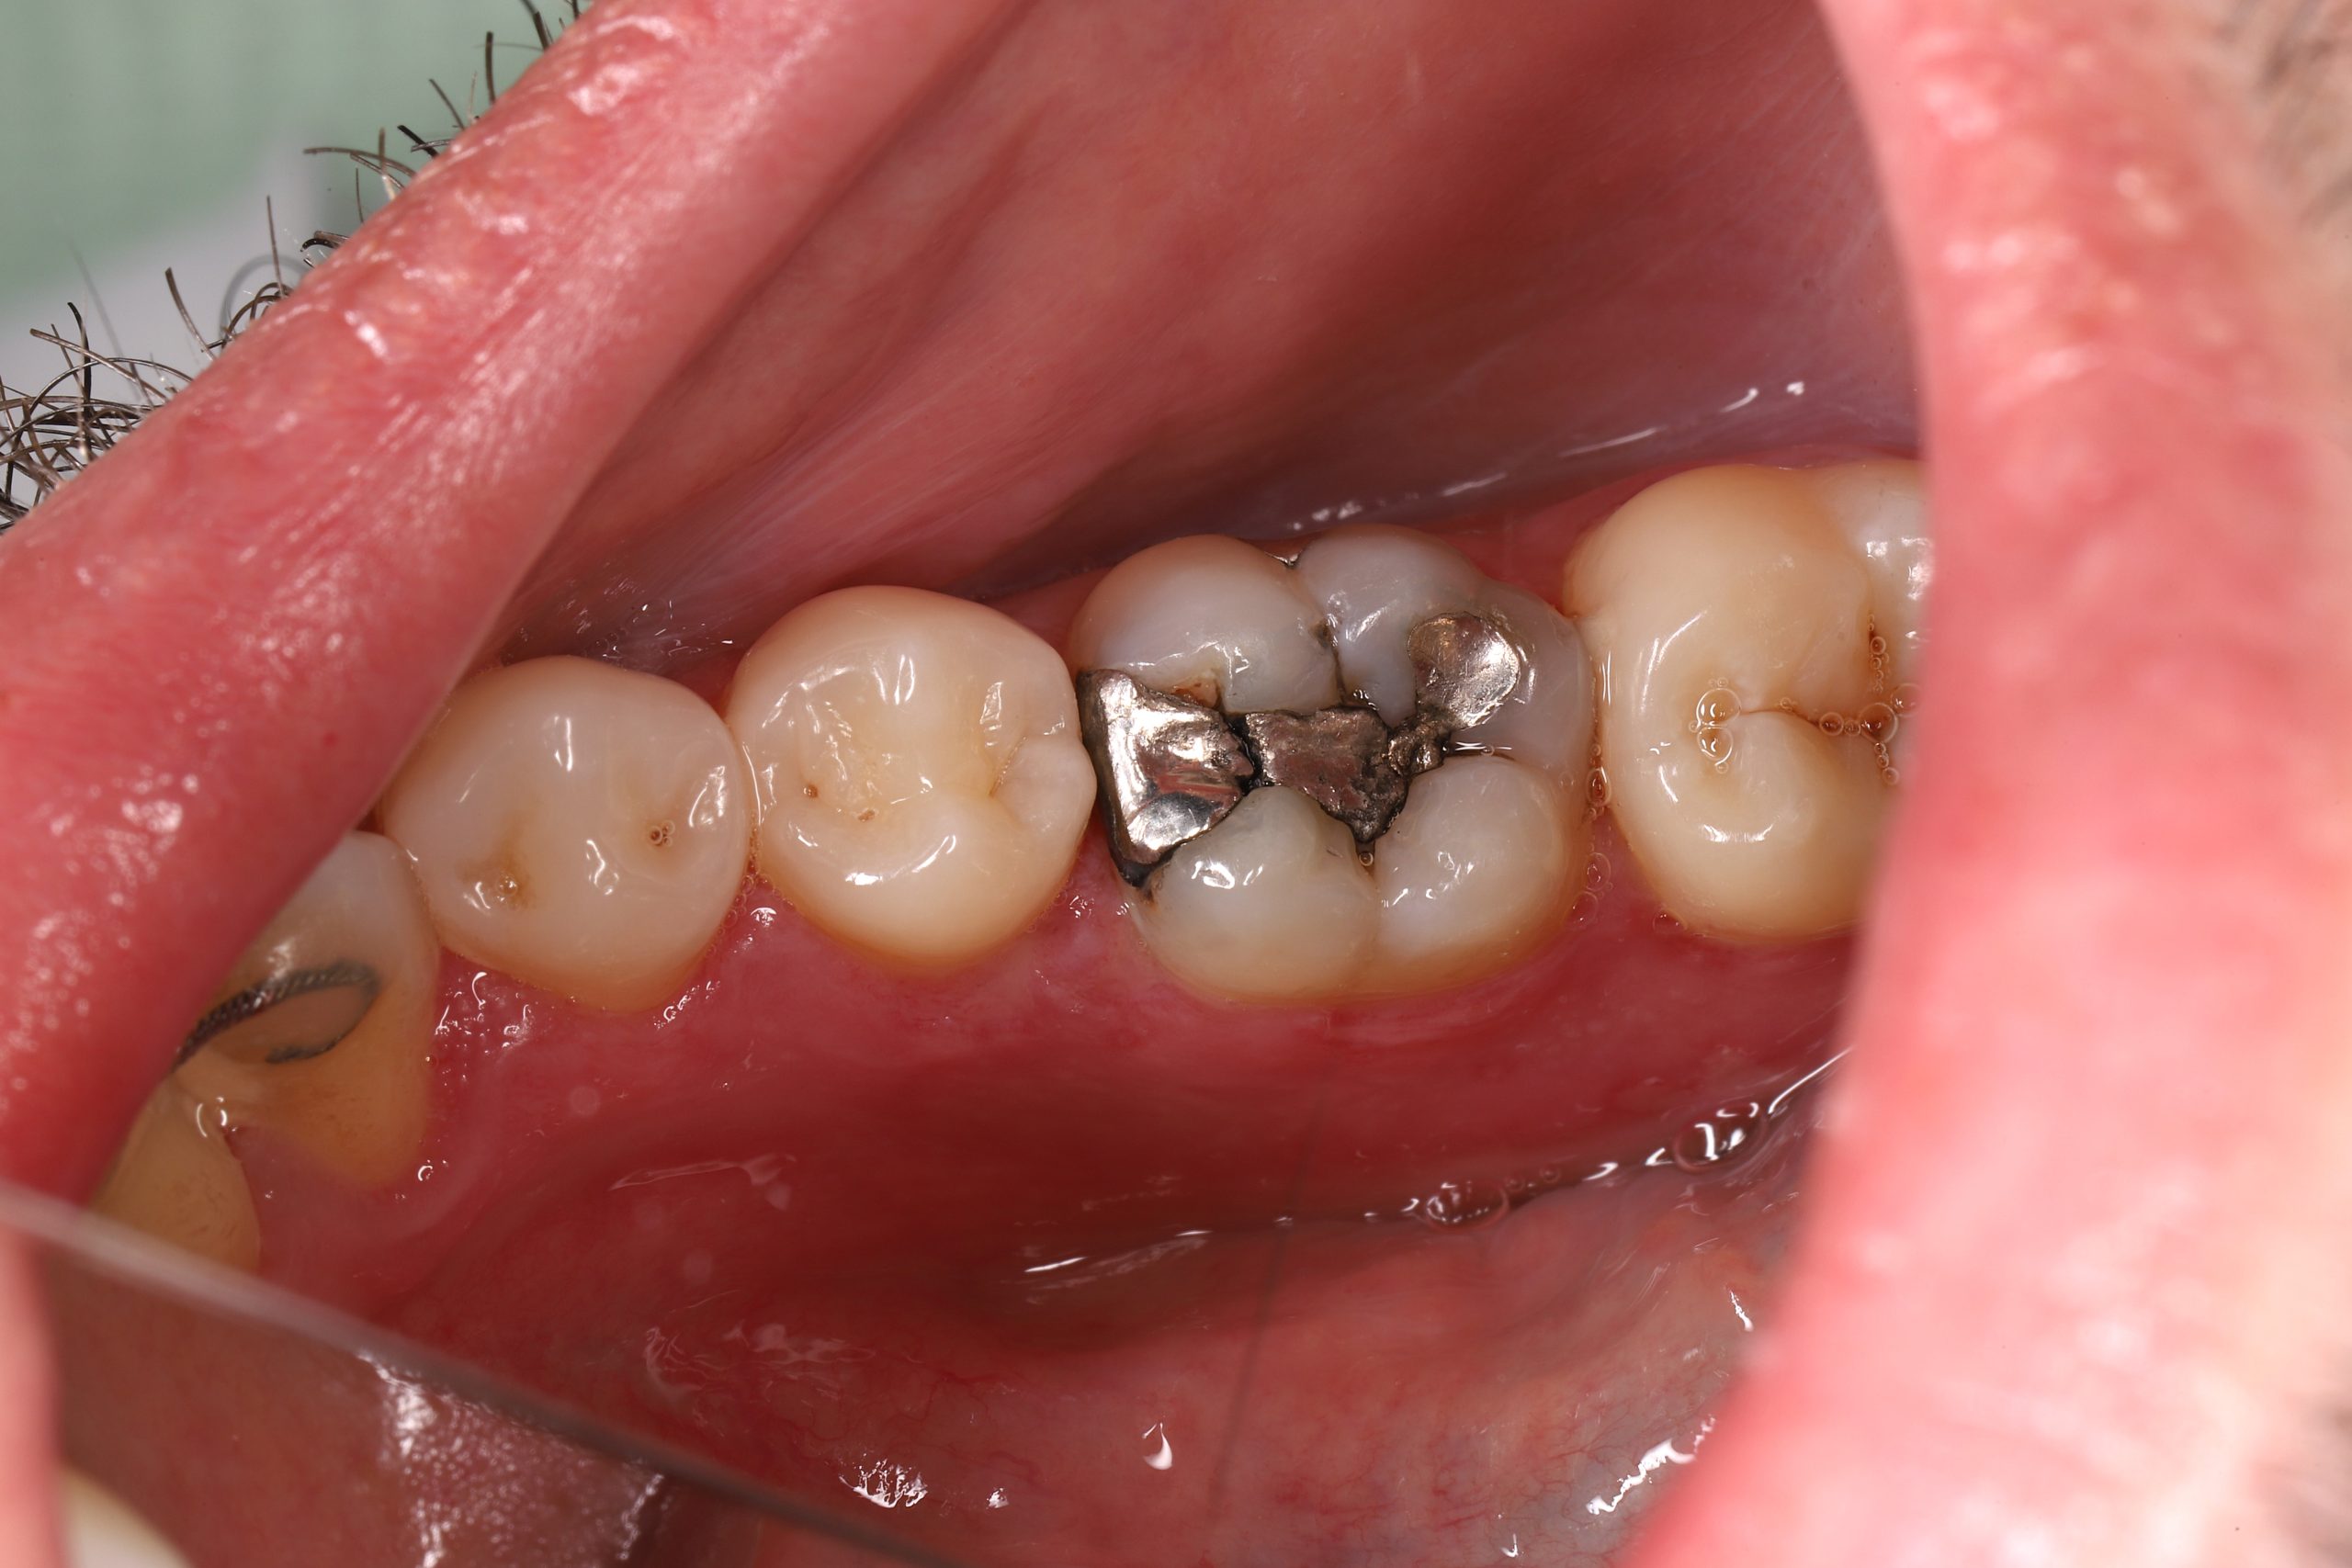

• replacing old metal fillings with a tooth-coloured option

We remove weakened or decayed tissue and clean the area thoroughly. The goal is to preserve as much healthy structure as possible.

Durable for Everyday Chewing